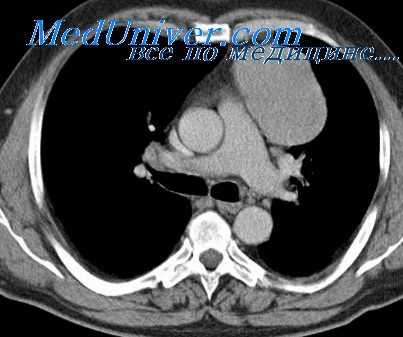

Закрытые повреждения средостения могут быть изолированными и комбинированными с повреждением костного скелета грудной клетки, чаще всего грудины и ключицы. Тяжелая травма может сопровождаться разрывом крупных сосудов средостения. Такие больные быстро погибают при явлениях сдавления органов средостения. В нашей практике мы имели одно наблюдение подобного вида.

Больной Ф., 45 лет, 21/IX 1997 г. получил тяжелую травму грудной клетки — был придавлен машиной к стене. В тяжелом состоянии, без сознания доставлен в больницу. При осмотре выраженный цианоз лица и верхней половины груди, кровоизлияния в белковые оболочки глаз. Дыхание неравномерное, частое — до 30 в минуту. Пульс едва определяется, артериальное давление: максимальное 60 мм, минимальное не регистрируется.

При осмотре и пальпации заметна деформация грудины на уровне четвертых реберных хрящей, где отмечается поперечный перелом тела грудины без значительного смещения отломков. Небольшая подкожная эмфизема в верхней половине груди спереди и в надключичных пространствах. При перкуссии выраженное притупление в правой половине грудной клетки, сливающееся со средостением.

Произведено переливание 500 мл крови, введены сердечные средства. Приступить к пункции правой плевральной полости не удалось из-за внезапной гибели больного.

На вскрытии обнаружен перелом тела грудины, разрыв дуги аорты в промежутке между безымянной и левой общей сонной артериями. Смерть наступила в результате кровоизлияния в средостение и сдавления его органов. Отмечается массивный правосторонний гемоторакс.